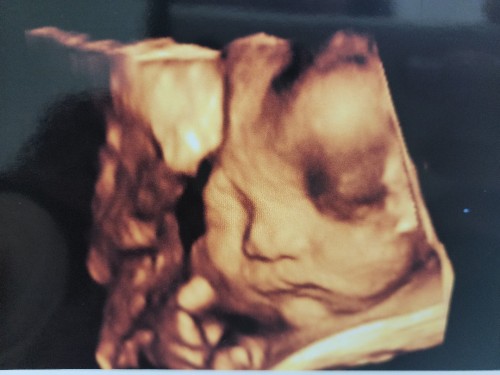

Ultrasound pic

Just want to ask if the ultrasound of my lil one is normal. Is there deficiency on her eyes or the that only blood? Thank you so much in advance. A little bit worried lang po..

Perhaps you might want to check with your gynae/doctor of the day with regards to the ultrasound picture. They will be more verified to answer your worries and thoughts.

The gynae will advise if there’s any cause for concern. If your gynae didn’t say anything it’s normal.